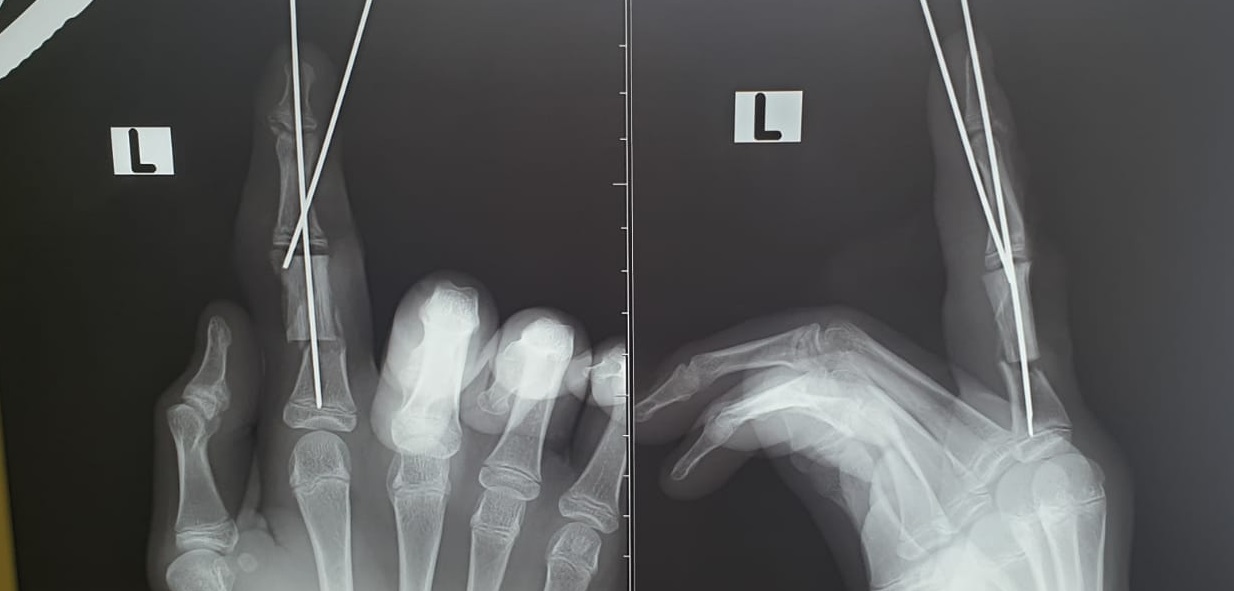

Как сообщили врачи, ребёнок работал на дачном участке и повредил «болгаркой» пальцы левой руки. Пострадавший обратился в травмпункт, откуда его направили в клинику Педиатрического университета.

- Мы диагностировали неполную травматическую ампутацию указательного пальца и скальпированные раны среднего пальца. Половина основной фаланги указательного пальца отсутствовала, она была размозжена. Палец держался на сосудисто-нервных пучках. Нам нечем было закрывать большой дефект кости, речь шла либо об укорочении пальца, либо о замещении поврежденного участка собственным фрагментом кости пациента - так называемой аутотрансплантации , - сообщил детский хирург Михаил Азаров. |

Операция продлилась более трёх часов и завершилась успешно. Мальчик продолжает лечение в клиники вуза.

- Важно понимать, что, так как пациент травмировал суставную поверхность, ему потребуется длительная реабилитация, и могут быть ограничения в подвижности пальца, - сообщил Михаил Азаров. |